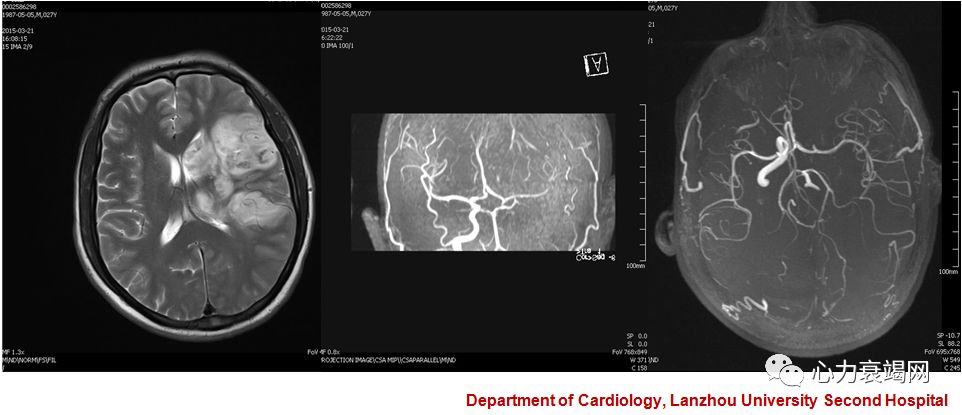

➤ 现病史:入院前10天,因离婚心情差开始饮酒,每天500ml,整日呈醉酒状态。于入院前1日,饮酒后出现右侧肢体无力伴意识不清呼之不应,被送往当地县级医院救治,头颅CT检查提示:左侧颞/顶叶低密度病灶,初步考虑为脑梗塞后转诊于我院。患者发病后有头晕及头痛,并有恶心伴呕吐胃内容物一次,为

1.急性脑血管病 脑梗死

2.急性脑血管病 脑梗死